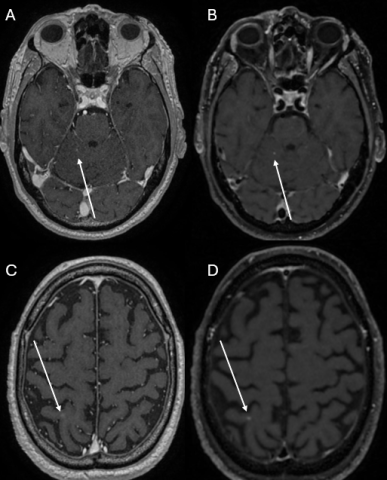

La séquence 3D T1w-SE a été privilégiée par rapport à la séquence 3D T1w-GRE en raison de son meilleur contraste après injection de gadolinium, permettant une détection plus sensible des métastases cérébrales, notamment des lésions de petite taille (figure 2).

Figure 2.png

Ces métastases punctiformes supra- et infratentorielles (flèches) étaient difficiles à détecter sur les séquences T1 pondérées en écho de gradient après injection (T1w-GRE) (A et C), tandis que leur détection était nettement plus aisée sur les séquences T1 pondérées en écho de spin après injection (T1w-SE) (B et D)